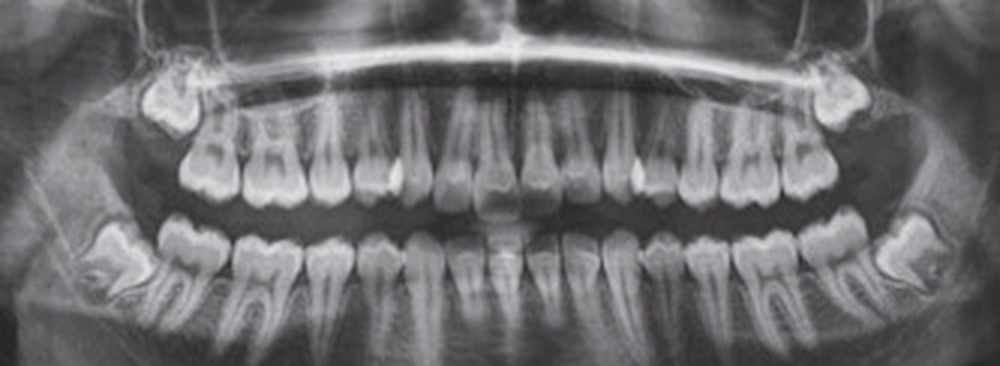

Sur le plan dentaire, elle présente une classe II d’Angle complète, une supraclusion de 4 mm et un surplomb de 6 mm ne correspondant pas au décalage de classe II molaire.

À la vue de l’examen radiographique, elle est au stade CS6 d’après la méthode de maturation vertébrale de Baccetti [1]. Elle présente une classe II squelettique de Ballard par rétrognathie mandibulaire avec un ANB de 9° et un AoBo de 9 mm sur un schéma facial normo-divergent. L’incisive mandibulaire est vestibulo-versée (IMPA = 114°). Le maxillaire est bien positionné. Elle présente de plus une dysharmonie dento-dentaire (DDD) antérieure par excès mandibulaire.